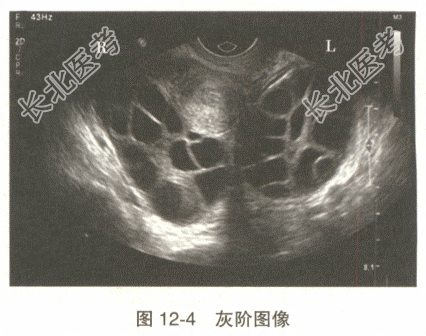

- 单项选择题患者女,27岁。IVF术后行盆腔超声检查, 发现双侧卵巢明显增大,呈多发囊肿样改变, 根据声像图表现(图12-4),最可能的诊断是

A、卵巢过度刺激综合征

B、卵巢黏液性囊腺瘤

C、多囊卵巢

D、卵巢黄素化囊肿

E、卵巢畸胎瘤